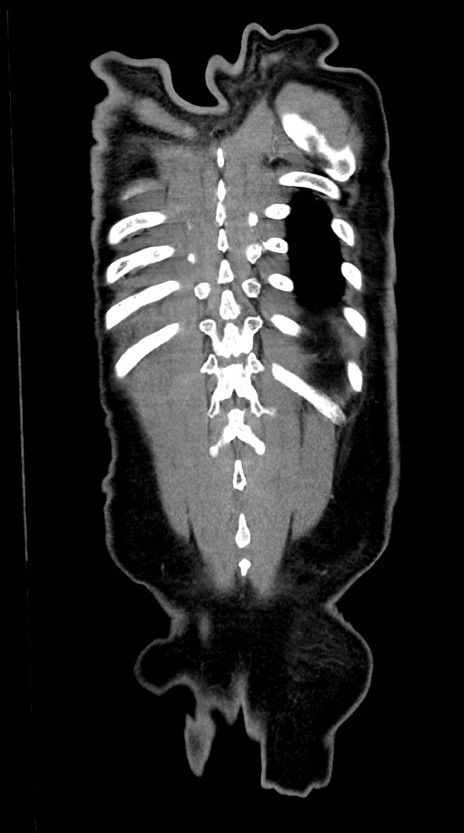

症例28(冠状断像)

【症例】60歳代男性

【主訴】嘔吐

【現病歴】胃癌にて胃全摘後。食思不振が悪化し、夜中に嘔吐することがある。

【既往歴】胃癌、胃全摘、脾摘、胆摘後

【データ】WBC 5900、CRP 10.56